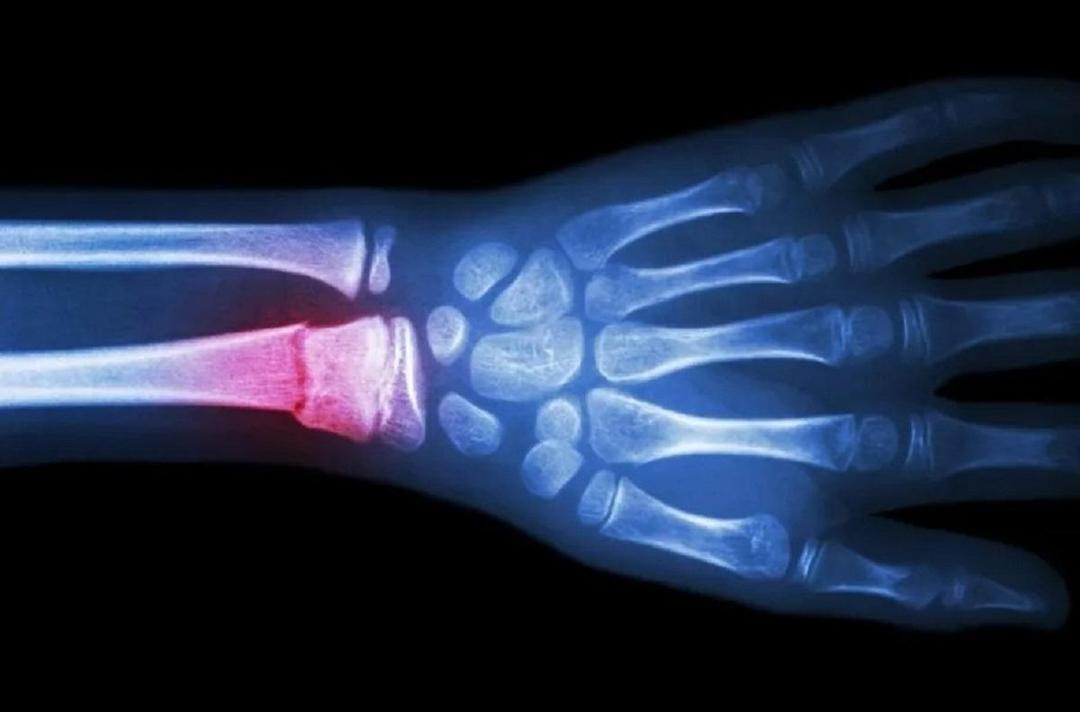

«تفنگ چسب» برای چاپ سهبعدی استخوان؛ ترمیم شکستگیها آسانتر میشودعصر ایران - 1404-06-26 06:00:0110 بازدیدسایرمحققان یک دستگاه شبیه به «تفنگ چسب» توسعه دادهاند که میتواند پیوندهای استخوانی را به صورت سهبعدی در محل شکستگی چاپ کند.اخبار مرتبط هند اسنپبک را دور زد؟/ روایت نماینده مجلس از خرید محموله نفت خام به ارزش ۱۱۱ میلیون دلار از ایرانخبرآنلاین - 1404-07-13 پروژه ساخت مدرنترین کشتی جنگی آلمان در معرض شکستمشرق نیوز - 1404-07-13 تحول تاریخی: طنین درخواست تحریم اسرائیل در پارلمان آلمانمشرق نیوز - 1404-07-13عصر ایرانلینک اصلی خبر